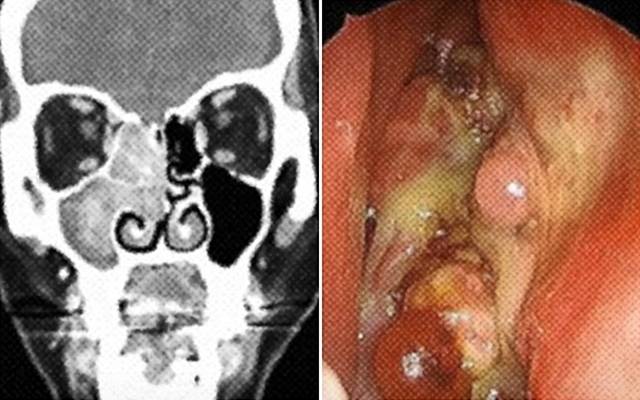

코 종양은 코 안쪽과 부비동, 비인두, 그리고 두개골 등에 발생하는 비정상적인 조직 덩어리를 말한다. 양성 종양인 경우도 있지만, 악성 종양일 경우 코 주변의 눈이나 뇌, 얼굴, 뼈까지 침범할 수 있어 관심이 필요하다.

코 종양 검사는 내시경으로 코 안을 들여다보는 비교적 쉬운 방법으로 가능하다. 이때 종양이 의심되면 조직검사나 CT 추가 시행으로 종양 여부 및 범위를 파악한다.